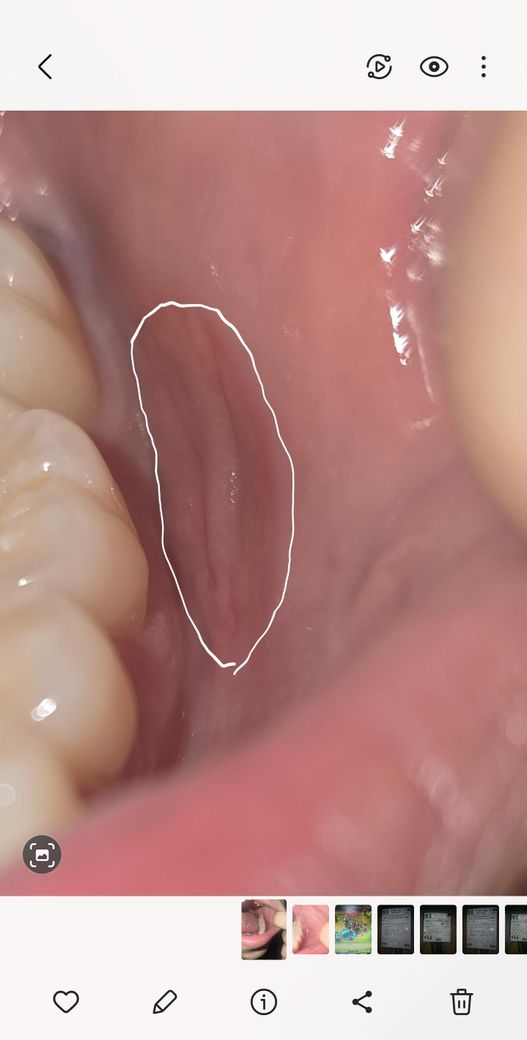

완쪽 볼 안 점막 염증 이게 구강암 일 수도 있나요?

아래 사진처럼 생긴지는 3주됐고 입을 벌려서 그런데 원래는 꼬불꼬불한 원형이고 통증은 거의 없습니다. 혀로 만져보면 볼 점막보다 질긴 느낌이 나고 사진보다 실제론 더욱 붉습니다. 자극(양치, 음주 등) 받으면 살짝 붓습니다.

사랑니도 위, 아래로 살짝 돌출 되어있습니다.

(위치 좋은 편 아님)

구강암 일 수도 있나요? 그리고 병원에서 정확하게 확인 할려면 뭐라고 질문해야되나요?